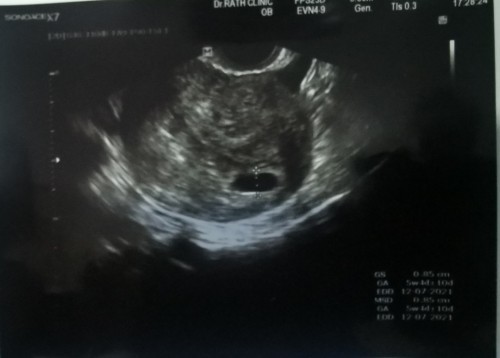

ในใบซาวน์เขียนว่า5สัปดาห์กว่าๆน่ะคะ บางทีไข่อาจจะตกช้าก็ได้คะ เห็นกำหนดคลอดในใบซาวน์ 17/7/2021น่ะ ของเรา9สัปดาห์กำหนดคลอด 19/6/2021 ใจเย็นๆน่ะคะคุณแม่รออีกนิด เดวก็เจอน้องแล้วคะ

อายุ41ค่ะ เคยแท้งไปเมื่อปีที่แล้วตอน 8-9สัปดาห์ ปีนี้ทำiui 2 ครั้งไม่ติด มาติดเองธรรมชาติ ตอนนี้อายุครรภ์ 8 สัปดาห์3วัน แต่ซาวด์เจอแต่ถุงตั้งครรภ์ ยังไม่เห็นตัวเด็ก (2 อาทิตย์ที่แล้วตอน6 สัปดาห์ยังไม่เจอก็แอบกังวล นับวันรอมาพบคุณหมอวันนี้ นึกว่าจะได้เจอกันซะที)แบบนี้คือท้องลมแล้วใช่ไหมคะ มีคุณแม่ท่านไหนซาวด์เจอหลัง8สัปดาห์ไหมคะ ยังพอมีความหวังอยู่ไหมคะ ใจคอไม่ดี จิตตกมากเลยค่ะตอนนี้ #ขอคำแนะนำหน่อยค่ะ #ขอบคุณสำหรับคำตอบค่ะ

ในใบซาว 5 week ไข่คุณแม่อาจตกช้า ใจเย็นๆรออีกนิดนะคะ น้องอาจจะยังอ่อนอยู่เลยยังไม่เจอ เราก็เคยผ่านจุดนี้มาแล้วค่ะ😄